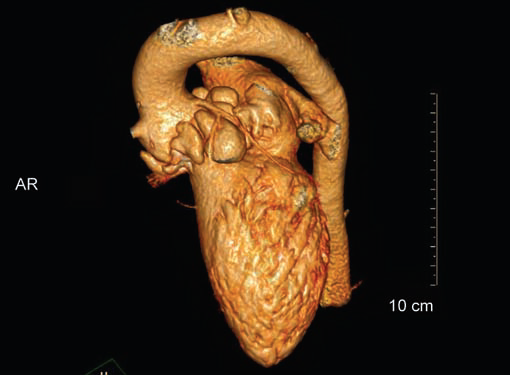

Any part of aorta can get affected by aneurysms. Focal

dilations can be saccular or fusiform. Atherosclerosis is

the most common cause. Tubercular and other infective

aneurysms, traumatic ones are also uncommonly seen. Size

of the aneurysm, proximity to origin of main vessels, relation

with branching and bifurcation, presence of mural thrombus

are the critical information sought on CT.

complication. Aneurysmal dilation is common in ascending

aorta (Figs 19W to Y).

CT is also useful in surveillance of diagnosed aneurysms.

Figs 19A to Y (A to C) Scannogram (A), plain (B) and contrast study (C) show partial anomalous pulmonary venous connection; (D to F) Heterotaxy; (G) Aortic occlusion; (H and I) Aortic stents; (J) Aortic dissection with ‘Benz’ sign due to second dissection within the true lumen; (K, L and M) Aortic dissection with thrombus in pseudolumen following catheter angiogram; (N) Aortic dissection involving common carotid arteries and subclavian artery; (O, P, Q and R) Aortic dissection with right renal artery arising from true lumen and left renal artery from false lumen; (S, T, U and V) Stanford B dissection with extension Y to iliac vessels; (W to Y) Aneurysmal dilation of ascending aorta